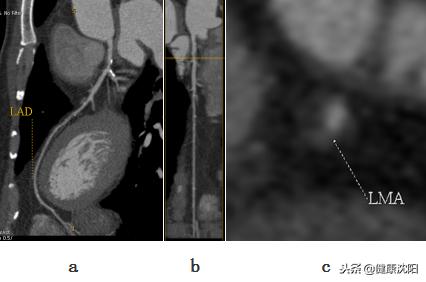

abc:冠脉CPR曲面图像、拉直图像及相应病变血管截面的探针图像

显示左冠脉血管的解剖形态及分布

显示冠脉与心脏VR主次重叠图像,可以反映冠脉的心肌供血区域对照